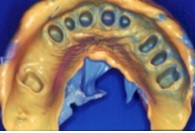

Impresión

tomada con boca abierta, cubeta de stock, masilla y ligero, dos tiempos.

Nótese la salud periodontal, que se traduce en una impresión perfecta y

por tanto, en un modelo de trabajo asimismo perfecto. |